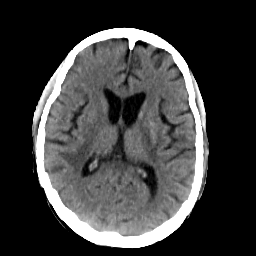

In this paper, we propose a bidirectional learning model, known as dual contrast cycleGAN (DC-cycleGAN), for medical image synthesis from unpaired data. Specifically, a dual contrast (DC) loss is formulated that leverages the advantage of samples from the source domain as negative samples to indirectly build constraints between real source and synthetic images via discriminators, and synthesize images more related to the target domain by enforcing the synthetic images to fall far away from the source domain. In addition, structural similarity index (SSIM) [35] and cross-entropy (CE) [48] are integrated into the DC-cycleGAN structure to avoid disappearing gradient information that is caused by a mean absolute error (MAE) and synthesizing irrelevant images. SSIM considers luminance [35] and CE converges fast as its back-propagation error is less than MSE [28]. As can be seen in Figs. 1 and 2, using SSIM and CE with dual contrast can generate more clear and accurate MR images as compared with that of MAE and MSE, and SSIM and CE without dual contrast loss. Although both SSIM and CE with dual contrast and without dual contrast generate similar CT images, SSIM and CE with dual contrast quantitatively generate better images as shown in Table 4. The experimental results indicate that DC-cycleGAN is able to consider more complex features such as structure in synthesizing images and produce remarkable results as compared with other state-of-the-art methods reported in the literature.

Tables 3 and 4 show the results of MR and CT synthesis, respectively. As can be seen, all components play vital role in both tables. SSIM & CE (w) performs significantly better than other losses in synthesizing MR images. This also can be seen visually in Fig. 1. In contrast, SSIM&CE (w) performs slightly better than SSIM&CE (wo) in synthesizing CT images, both generate more or less similar CT images (see Table 4).